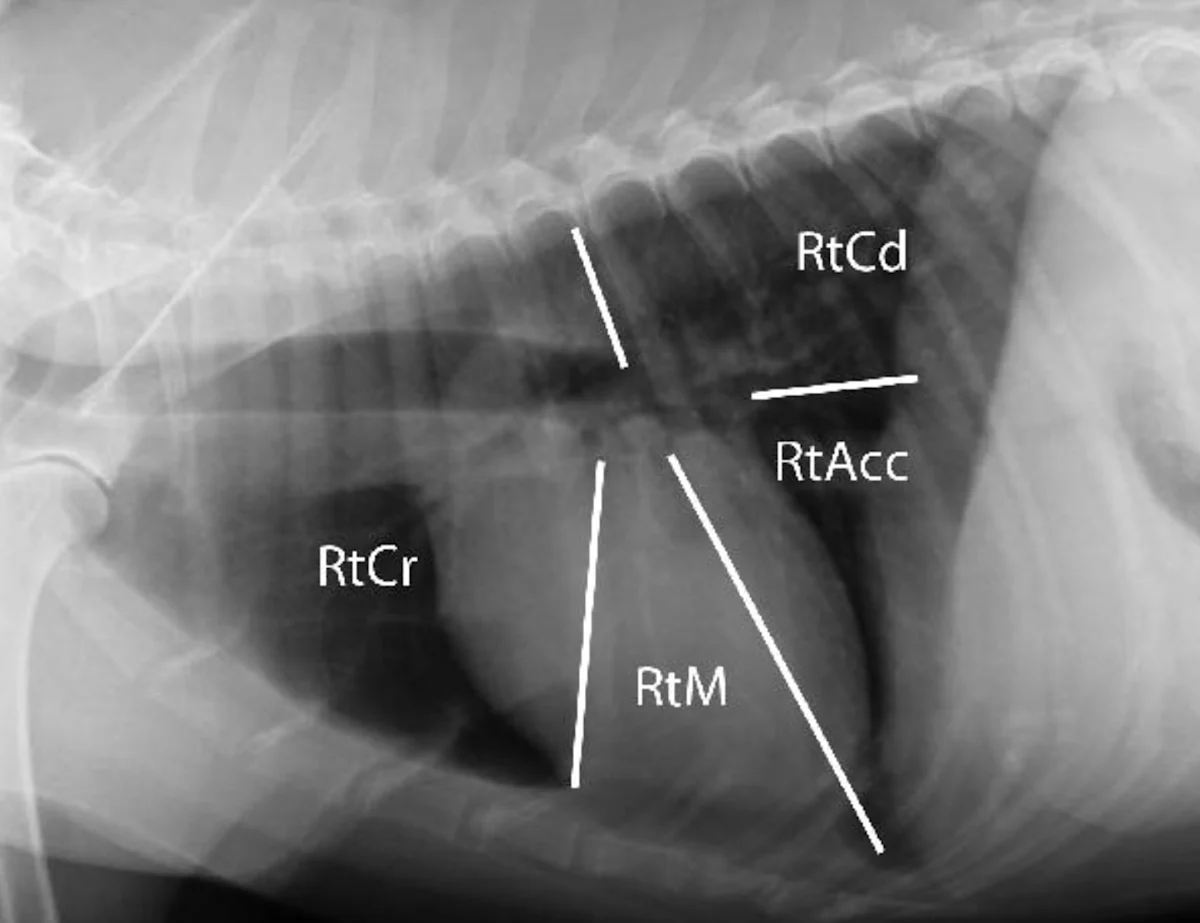

Step 2: Pleural Space

The pleural space should not be seen on thoracic images from normal animals. A very small amount of fluid, normally present between the visceral and parietal pleura, is imperceptible on thoracic radiographs; however, the pleural fissure lines or interlobar fissures may still be seen within very specific locations (Figure 3).

Right lateral (A) and ventrodorsal (B) radiographs from the same dog shown in Figure 2 with the expected locations of the interlobar fissures noted.